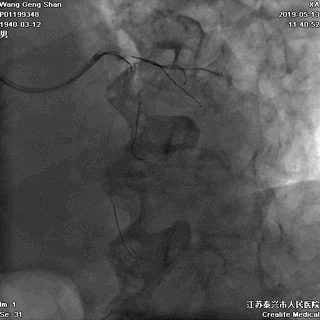

05 LM-LAD支架植入

右头位定位

蜘蛛位定位

LCX球囊拘禁,主支支架释放

回撤LCX球囊